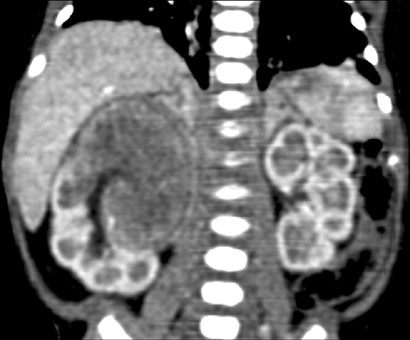

Renal Tumors Of Childhood Radiologic Pathologic Correlation Part 1 The 1st Decade From The Radiologic Pathology Archives Radiographics